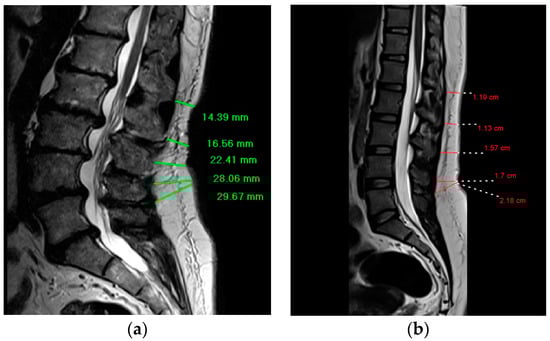

2.2. Lumbar Magnetic Resonance Imaging

2.3. Dorsal Subcutaneous Fat Thickness Measurements